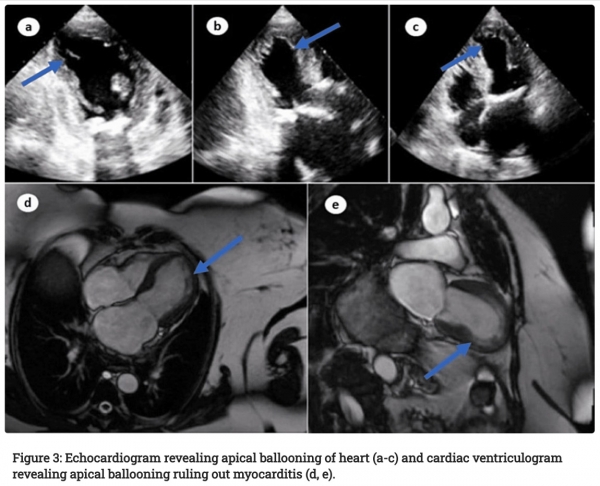

Testi na Covid-19 so ostali negativni. EKG in transtorakalna ehokardiografija sta pokazala jasne motnje v delovanju srca, zdravniki pa so na rentgenskem slikanju odkrili tudi pljučni edem. Bolnik je trpel zaradi stalne tahikardije in nihanja krvnega tlaka. Ob tem je padla v šok. Pljučno embolijo in trombotične ali obstruktivne lezije v koronarnih žilah je bilo mogoče izključiti, vendar je MRI razkril očitno baloniranje srca, ne pa tudi miokarditisa. Na podlagi tega in prejšnjega cepljenja proti koroni so zdravniki postavili diagnozo TCM – drugega vzroka resnih težav s srcem ni bilo mogoče najti.